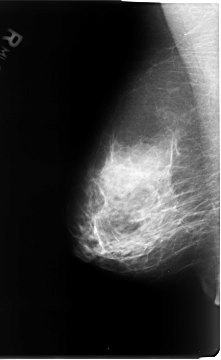

B_3072_1.RIGHT_MLO

RIGHT_MLO LINES 4672 PIXELS_PER_LINE 2872 BITS_PER_PIXEL 12 RESOLUTION 50 NON_OVERLAY